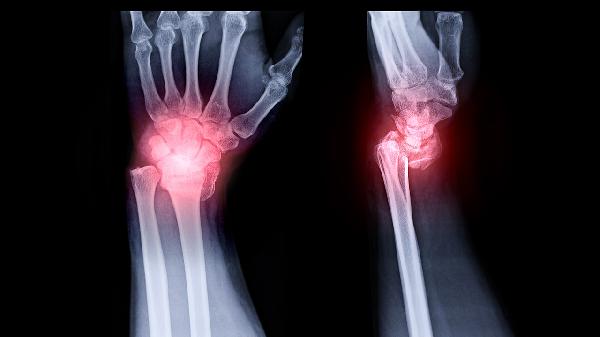

腕部骨折后如何锻炼

腕部骨折后可通过被动活动、主动活动、抗阻训练、功能性训练、器械辅助等方式锻炼。腕部骨折通常由外伤、骨质疏松、重复应力等因素引起。